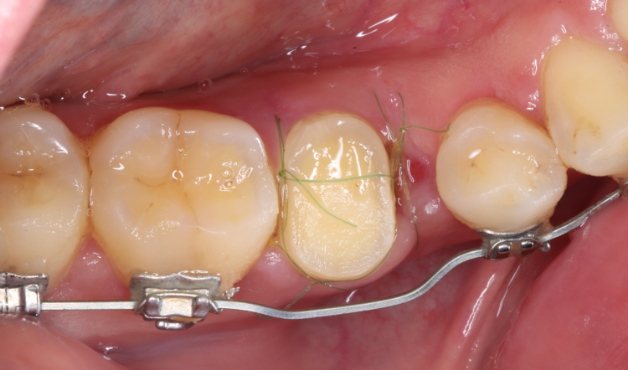

Under Treatment

主訴

歯を残せないと言われた。インプラントは先延ばしにしたい

治療内容

自家歯牙移植 / イニシャルトリートメント(大臼歯)レジンコア

治療期間

2ヶ月

治療費用

308,000

治療の

リスク

術後しばらくしてから骨性癒着、外部吸収を起こす可能性があります。